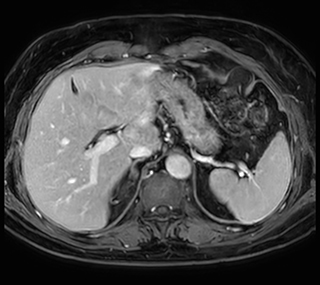

Free breathing abdominal MRI with VitalEye

Ascites can be hard to image, but excellent result is obtained with Ingenia Ambition. This high resolution image demonstrates the high quality that can be obtained with VitalEye and the patient just breathing normally. The acquisition time is fast thanks to the accuracy of the respiratory gating with VitalEye** and it also saves the time needed to put a respiratory belt on the patient.

MCVI VitalEye abdomen

3D T2 with VitalEye

MCVI VitalEye ascites